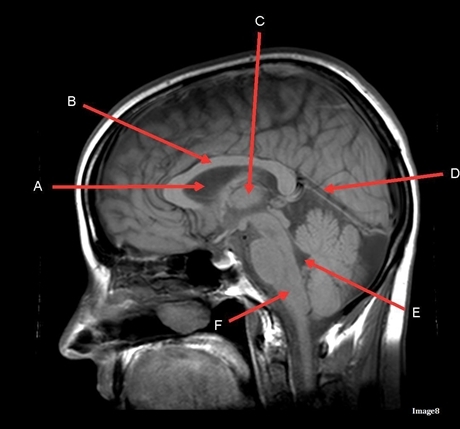

Image weighting and axis

T1 Sagittal

A

Lateral Ventricle

B

Corpus Callosum

C

Thalamus

D

Tentorium

E

4th Ventricle

F

Medulla Oblongata

Genu Corpus Callosum

Splenium Corpus Callosum

Pons

Cerebellum